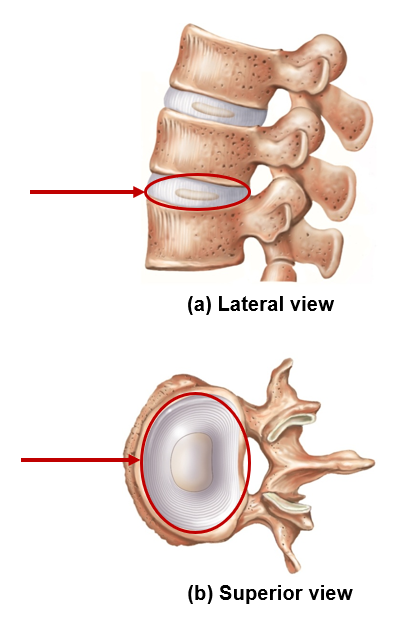

Features of intervertebral disc

Shock absorber

Nucleus pulposus

Anulus fibrosus

Nucleus pulposus

Internal, gel-like core, shock absorber

Anulus Fibrosus

External, tougher ring, strength